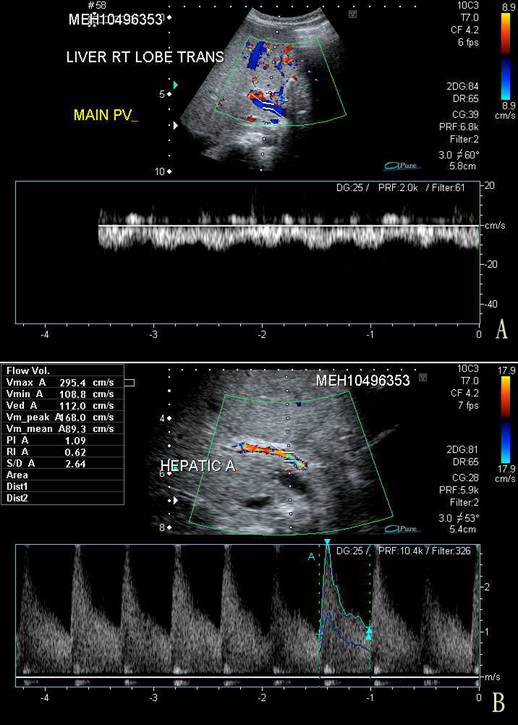

On the third day of admission, her condition deteriorated with recurrence of vomiting, abdominal pain, and abrupt onset of abdominal distention, with a weight gain of 0.5 kg from the baseline of 9.5 kg. The liver was palpable at 3 cm below the costal margin and was firm in consistency. Spleen tip and signs of shifting dullness were detectable. There was persistent severe thrombocytopenia despite platelet transfusion on the day of admission. Serum ALT and AST were grossly elevated at 746 u/L and 1,660 u/L, respectively, and albumin dropped to 26 g/L. Prothrombin time was prolonged at 16.7 s (normal, 10-14 s) while partial thromboplastin time (40.7 s) was still within normal limits. An urgent ultrasonography and Doppler examination of the liver revealed hepatosplenomegaly and gross ascites. Blood flow in the portal vein was reversed (Fig. 1). The resistance in the hepatic artery was increased with peak systolic velocity of 2.95 m/s (normal, 0.4 m/s) and a resistive index of 0.67. Small bilateral pleural effusions were present.

Figure 1

A. Trans-abdominal sonography and Doppler study of the right lobe of the liver showing centrifugal blood flow in the main portal vein (in blue) compared to the hepatic arterial blood flow (in red). B. Doppler study of the hepatic artery showing a markedly increased peak velocity of 2.95 m/s.